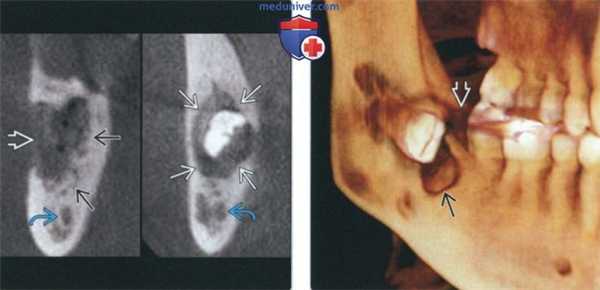

(Слева) На аксиальной КТ с КУ в нижней челюсти справа определяется большая опухоль, распространяющаяся в прилежащие мягкие ткани. Имеет место лучистая периостальная реакция со стороны щечной поверхности нижней челюсти. Такая же картина наблюдается при остеосаркоме.

(Справа) На аксиальной КТ с КУ в нижней челюсти слева определяется плохо отграниченная лимфома Беркитта, виден сопутствующий мягкотканный компонент. Визуализируется также крупный некротический задний шейный лимфоузел.